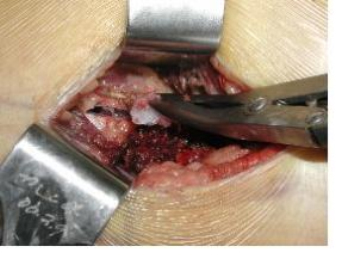

절개 생검(incisional biopsy)시에는 정확한 생검 부위를 선택하며, 충분한 양의 조직을 채취하고, 부위에 따라 종양의 분화도가 다를 수 있으므로 필요에 따라 2-3개 장소에서 채취합니다.

[ 절개 생검 ]

현미경학적인 검사 외에 면역조직화학검사, 전자현미경 검사, 세포유전학적 검사 등을 통해 최종 진단을 결정하게 됩니다. 종합적인 방사선 검사 소견은 조직검사의 계획 수립이나 병리 의사의 진단 결정에 도움이 됩니다. 병리의사는 임상소견과 방사선 검사소견 그리고 수술의사의 소견을 종합하여 최종 진단을 수립합니다.